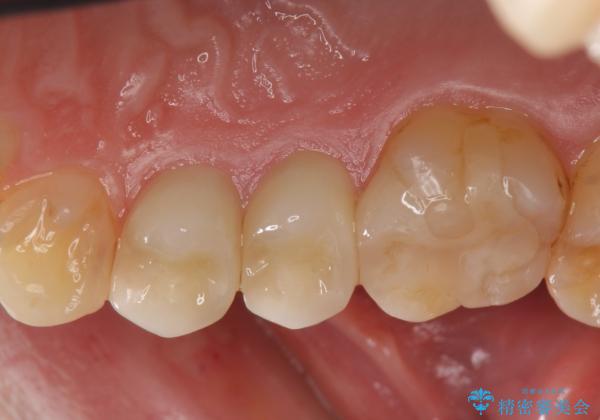

- 右上の銀歯を白くしたいといらっしゃった方の症例です。

右上4、5番目の歯はオールセラミッククラウンによる補綴、6番目の歯はセラミックインレーによる修復を行いました。

セラミックインレーについて

当院のセラミックインレーはemaxという強度と審美性に優れた材料を使用しています。

またプレス方式でインレーを製作しているため、削り出しで製作するCADCAMより優れた適合性も持ち合わせており、虫歯が再発しにくい修復物です。